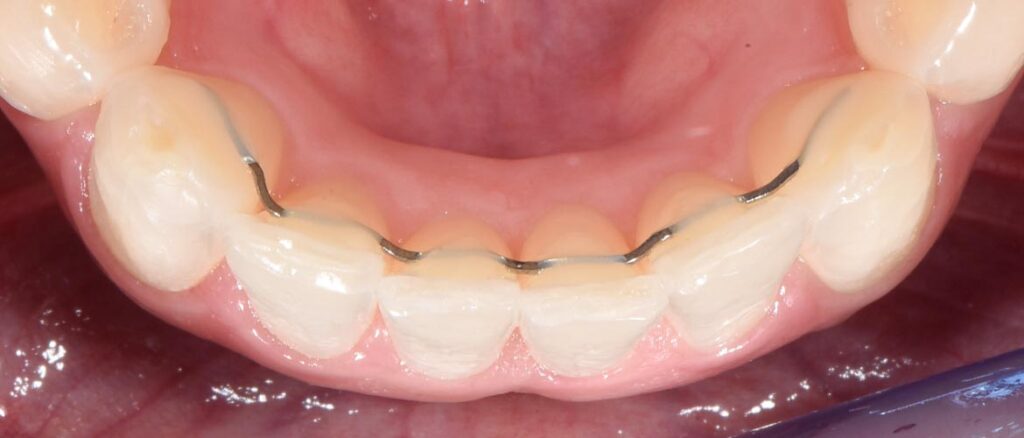

This is the gold standard of retention. A thin, custom-contoured wire is bonded to the inside of the front teeth (usually from canine to canine).

Präziser fester Retainer an der Unterkiefer-Front, hergestellt durch unseren innovativen Biegeroboter für maximale Passgenauigkeit

Successful resolution of frontal crowding in the lower jaw using Invisalign. The result shown is stabilized in the long term by a fixed lingual retainer.